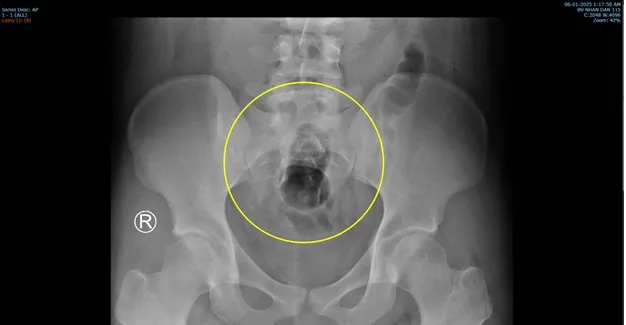

Sau khi thăm khám và chụp X-quang, bác sĩ xác định dị vật nằm sâu trong trực tràng. Người bệnh được gây mê nội khí quản để ê-kíp phẫu thuật lấy dị vật qua đường hậu môn. Kết quả ghi nhận, dị vật là một chai gel rỗng, không có điểm giữ bên ngoài nên dễ dàng trôi sâu qua hậu môn, gây đau đớn.